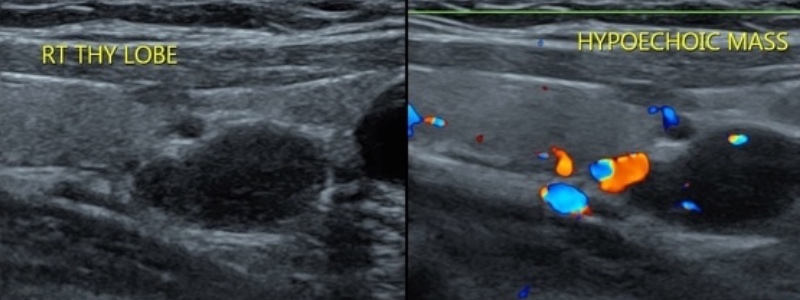

- 80% adénome parathyroïdien > 15% hyperplasie > 5% carcinome

- nodule hypoéchogène homogène > 1 cm + vascularisation

- à confronter à scintigraphie MIBI / TEP choline